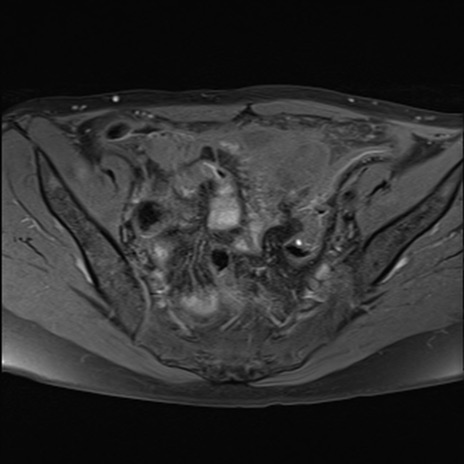

症例39 脂肪抑制T1WI(横断像)

MRI(4日後)

T1WI(横断像)